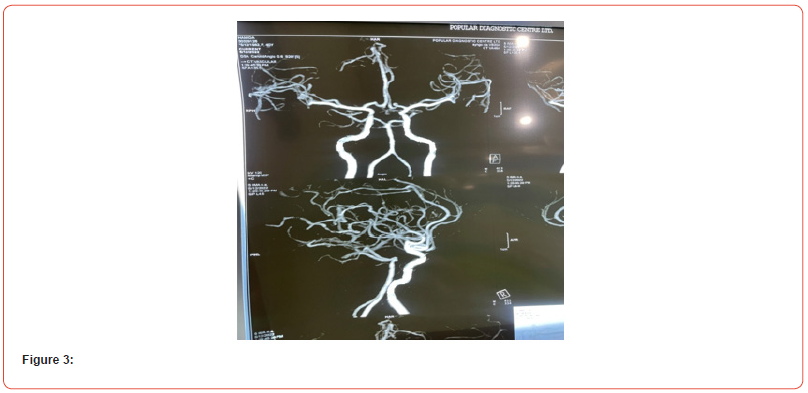

Her initial laboratory tests showed white blood cell count, 9.400/ml; red blood cell count, 4.56×10/μl; hemoglobin, 13.1 g/ dl; platelets 183×103; ESR 89 mm in 1st hour. Glucose, 82 mg/dl, blood urea nitrogen, 10 mg/dl; creatinine, 0.83 mg/dl; ELISA for HIV, negative; D-Dimer, 351 ng/ml (<500 ng/ml). Thyroid function tests showed TSH, 1.81 μUI/ml (0.34-5.60); free T3, 3.64 pg/ml (2.50 - 3.90); free T4, 0.96 ng/ dl (0,54-1.64). The cerebral spinal fluid reported 4 mononuclear cell/uL; glucose, 69 mg/dl; proteins, 55 mg/dl; ADA and PCR in CFS for tuberculosis were negative. ANA was positive in cytoplasmic pattern 1:40; anti-ds DNA, ENA profile, c-ANCA and p-ANCA were negative. CT scan of brain and paranasal sinus, MRV and MRA of the brain were normal (figure 3). (SOV) thrombosis was seen. MRI of brain with orbit with contrast was done in multiple axial, coronal and sagittal sections which showed iso to hypo-intense lesion in right cavernous sinus extending up to right superior orbital fissure (figure 2). The lesion was brilliantly contrast enhancing and causing significant compression of the neurovascular structure of right cavernous sinus. Both optic nerves were spared. ICA was also normal in diameter (Figure 2 & 3).

Figure 2 and figure 3 showing Axial MRI Brain T1W image reveals intense enhancement of the soft-tissue mass within the right cavernous sinus (black arrow) and normal MRA of brain respectively. Since the studies showed no abnormalities and we excluded neoplasic, infectious, vascular, thyroid and metabolic causes of painful ophthalmoplegia, we decided to start treatment for Tolosa- Hunt Syndrome with metilprednisolne 1 gr IV daily for 3 days, and noticed significant response of the right periorbital pain, palpebral ptosis and the ipsilateral ocular motor nerve palsies in next 2 weeks. At day 4, we changed treatment to prednisone at 1 mg/kg daily. Two weeks later, we initiated steroid tapering every week, and at week 12 the patient was asymptomatic and her neuro- ophthalmologic examination was completely normal.(Figure 4). The probable diagnosis of Tolosa–Hunt Syndrome was retained in the face of the negativity of all investigations carried out as well as spectacular response to treatment (Figure 4).

These have been described as “segmental narrowing”, “slight irregularity”, or “constriction”, and will resolve with corticosteroid therapy. The role of noninvasive vascular MRI techniques (MR angiography and venography) has not been defined in patients with the syndrome but these may prove to be valuable adjuncts in diagnostic evaluation.